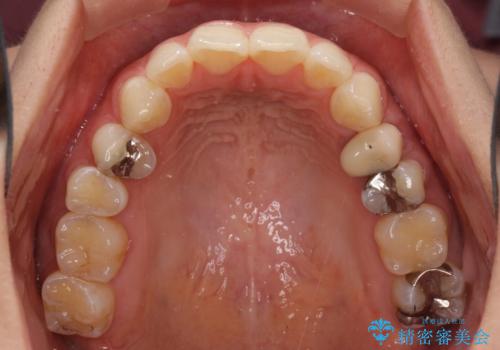

八重歯の再矯正 インビザラインでストレスなく矯正治療

- 学生の頃に矯正治療を行ったものの、保定を怠けてしまったことによる後戻りを気にして来院された患者様です。

根管治療が必要な歯があったため、矯正治療前に根管治療を行い、その後はインビザラインにより矯正治療を行うこととしました。

矯正治療後には根管治療を行った歯の補綴治療を行うこととしました。

下顎の八重歯が上顎歯列に収まる過程で咬みにくさがありましたが、最終的には、咬み合わせも安定し、きれいに歯列を整えることができました。